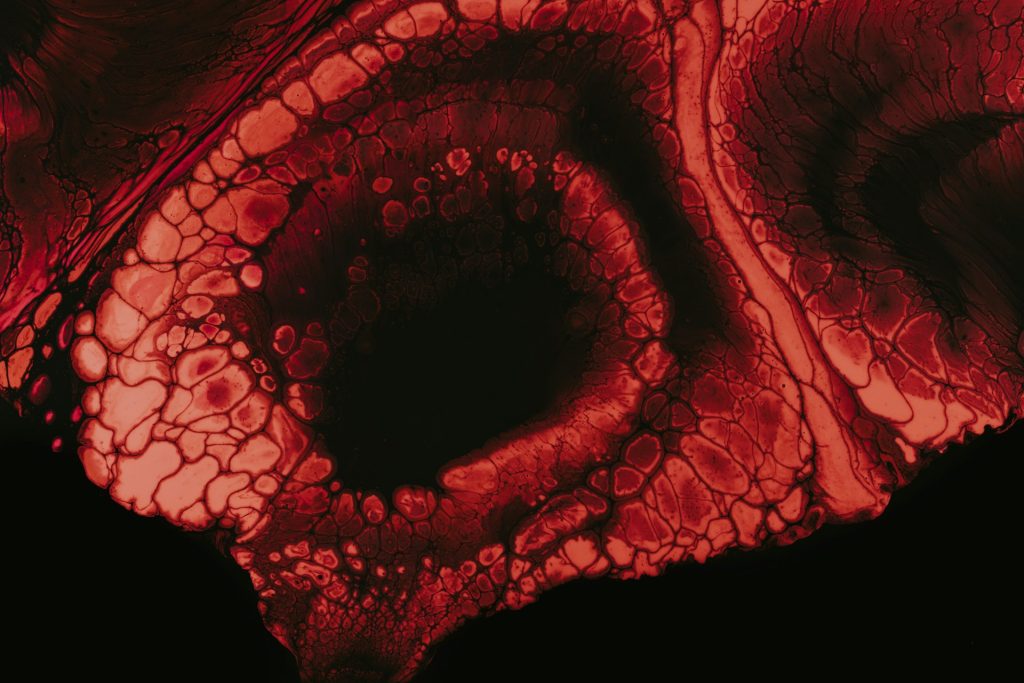

Hemofilia merupakan kendala pembekuan darah yang diakibatkan oleh minimnya aspek pembekuan tertentu dalam badan. Wajarnya, darah hendak mengeras buat menghentikan perdarahan dikala terjalin cedera. Tetapi, pada pengidap hemofilia, mekanisme ini tidak berjalan sempurna sehingga darah susah menyudahi mengalir serta resiko perdarahan jadi jauh lebih besar.

Secara universal, hemofilia dipecah jadi 2 tipe utama, ialah hemofilia A serta hemofilia B. Hemofilia A diakibatkan oleh kekurangan aspek VIII, sebaliknya hemofilia B diakibatkan oleh kekurangan aspek IX. Walaupun berbeda tipe aspek yang kurang, indikasi yang timbul kerap kali nampak seragam serta senantiasa memerlukan perawatan spesial.